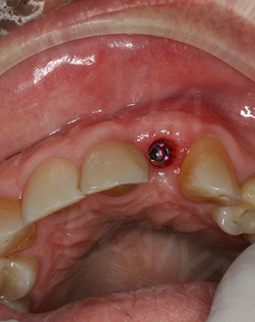

今年的4月18日,我去了第一次复诊后,直接飞回了加拿大。坐飞机过程也没有什么不适感,而且有按照郑院长的要求,一直在好好的呵护我的种植牙。现在回到中国,手机上显示客服的复诊短信提醒,虽然在还未种完牙的情况下,但这丝毫不影响我继续享用美食。复诊的时候,拍了片子,郑院长说植入的植体与骨结合不错,然后给我安装了愈合基台,说我有什么不适的话,都可以过来。

今天又来复诊,愈合基台无松动,可以戴牙冠了,取模也很方便,然后还有比色,一颗种植牙看着只是种牙而已,其实每个环节还是挺细心的,这次复诊刚好碰上活动,在此祝福生日快乐,也希望更多的缺牙人能在这里重拾口福健康!